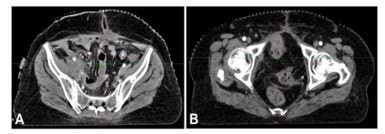

Figure 2: CT Images Demonstrating Progression of the Pelvic Mass Following Initial Chemotherapy

This follow-up CT shows significant tumor enlargement despite chemotherapy, justifying the treatment change to MVAC and confirming the aggressive disease course. Histopathological analysis of the resected mass confirmed transformation into enteric-type adenocarcinoma with perineural and lymphovascular invasion but no lymph node metastases. Consequently, adjuvant radiation therapy was administered to enhance local disease control.